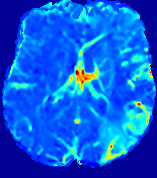

LesionRefer to captionRefer to captionRefer to captionRefer to captionRefer to captionRefer to caption𝐕rgbsubscript𝐕𝑟𝑔𝑏{\bf{V}}_{rgb}Refer to captionRefer to captionRefer to captionRefer to captionRefer to captionRefer to caption𝐕2subscriptnorm𝐕2{\|\bf{V}}\|_{2}Refer to captionRefer to captionRefer to captionRefer to captionRefer to captionRefer to captionRefer to caption3.53.53.52.82.82.82.12.12.11.41.41.40.70.70.70.00.00.0(mm/s)𝑚𝑚𝑠(mm/s)D𝐷DRefer to captionRefer to captionRefer to captionRefer to captionRefer to captionRefer to captionRefer to caption0.0200.0200.0200.0160.0160.0160.0120.0120.0120.0080.0080.0080.0040.0040.0040.0000.0000.000(mm2/s)𝑚superscript𝑚2𝑠(mm^{2}/s)Slice #1Slice #2Slice #3Slice #4Slice #5Slice #6

Figure 3: PIANO feature maps for one stroke patient, where the lesion is located in the left hemisphere. Top row: segmented stroke lesion region (white) on different slices, obtained from ISLES 2017. The corresponding slices for the PIANO feature maps are shown in the following rows.

For a better insight into an estimated velocity field 𝐕𝐕{\bf{V}} and diffusion field 𝐃𝐃{\bf{D}}, we compute the following maps: (1) 𝐕rgbsubscript𝐕𝑟𝑔𝑏{\bf{V}}_{rgb}: Color-coded orientation map of 𝐕=(Vx,Vy,Vz)T𝐕superscriptsuperscript𝑉𝑥superscript𝑉𝑦superscript𝑉𝑧𝑇{\bf{V}}=(V^{x},V^{y},V^{z})^{T}, obtained by normalizing 𝐕𝐕{\bf{V}} to unit length and mapping its 3 components to red, green, blue respectively; (2) 𝐕2subscriptnorm𝐕2\|{\bf{V}}\|_{2}: 222 norm of 𝐕𝐕{\bf{V}}; (3) D𝐷D: scalar field in Eq. 5.

Fig. 3 and Fig. 4 show the PIANO feature maps estimated from two ISLES 2017 patients: all are highly consistent with the lesion in both cases. Details of the blood flow trajectories are revealed in 𝐕rgbsubscript𝐕𝑟𝑔𝑏{\bf{V}}_{rgb} by the ridged patterns and the sharp changes of colors in the unaffected (right) hemisphere, while the flat patterns appearing within the lesion provide little directional information about the velocity and indicate low velocity magnitudes. Velocity magnitudes are more directly visualized via 𝐕2subscriptnorm𝐕2\|{\bf{V}}\|_{2}, from which one can easily locate the lesion where 𝐕2subscriptnorm𝐕2\|{\bf{V}}\|_{2} is low. D𝐷D also indicates lower diffusion values in the lesion, though with less contrast potentially due to the fact that it captures the accumulated effect of CA diffusion at the voxel-level.